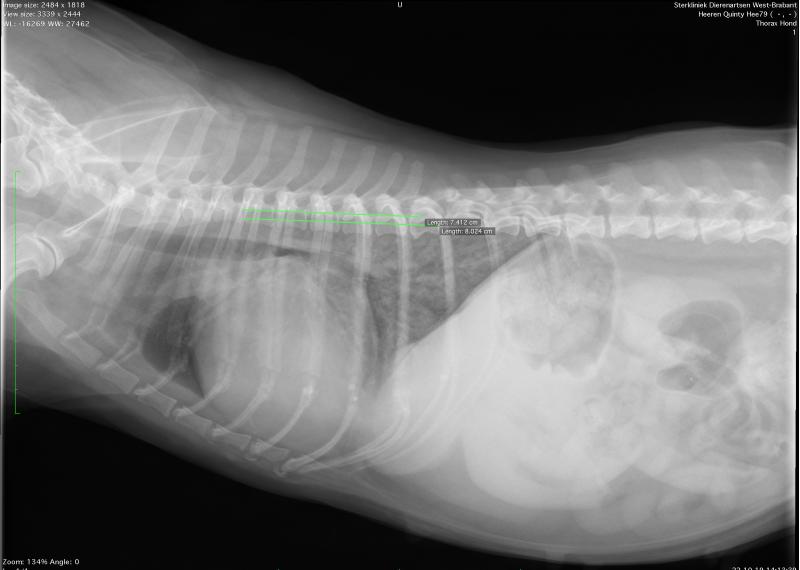

Een goed functionerend hart is van vitaal belang. Wanneer uw hond last heeft van verminderd uithoudingsvermogen, benauwdheid of flauwtes, dan bent u bij WB Dierenartsen in deskundige handen. Door middel van een lichamelijk onderzoek, röntgenfoto’s en in sommige gevallen ook een echo en een bloedonderzoek, kunnen we vaak zelf een diagnose stellen.